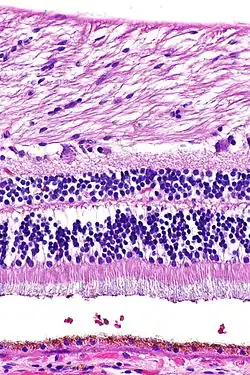

H&E stain

Hematoxylin and eosin stain (or haematoxylin and eosin stain or hematoxylin–eosin stain; often abbreviated as H&E stain or HE stain) is one of the principal tissue stains used in histology.[1][2][3] It is the most widely used stain in medical diagnosis[1] and is often the gold standard.[4] For example, when a pathologist looks at a biopsy of a suspected cancer, the histological section is likely to be stained with H&E.

H&E is the combination of two histological stains: hematoxylin and eosin. The hematoxylin stains cell nuclei a purplish blue, and eosin stains the extracellular matrix and cytoplasm pink, with other structures taking on different shades, hues, and combinations of these colors.[5][6] Hence a pathologist can easily differentiate between the nuclear and cytoplasmic parts of a cell, and additionally, the overall patterns of coloration from the stain show the general layout and distribution of cells and provides a general overview of a tissue sample's structure.[7] Thus, pattern recognition, both by expert humans themselves and by software that aids those experts (in digital pathology), provides histologic information.

Hematoxylin principally colors the nuclei of cells blue or dark-purple,[6][15][14] along with a few other tissues, such as keratohyalin granules and calcified material. Eosin stains the cytoplasm and some other structures including extracellular matrix such as collagen[5][7][14] in up to five shades of pink.[8] The eosinophilic (substances that are stained by eosin)[5] structures are generally composed of intracellular or extracellular proteins. The Lewy bodies and Mallory bodies are examples of eosinophilic structures. Most of the cytoplasm is eosinophilic and is rendered pink.[10][15] Red blood cells are stained intensely red.